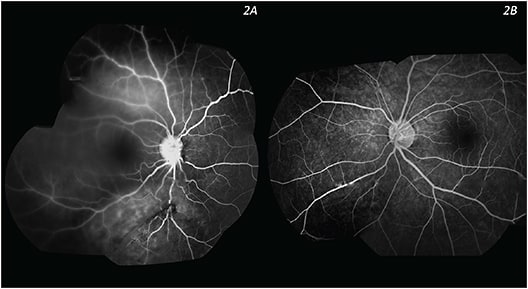

Fluorescein angiography showed early ischemia and late diffuse leakage from the fibrovascular tissues (Figure 2). Orbital ultrasound was performed and did not reveal optic nerve head drusen. Her complete blood counts, routine serum biochemistry, and C3 and C4 levels were within normal limits. Lupus anticoagulant, anticardiolipin antibody, rapid plasma regain, anti-Toxoplasma IgM, anti-Toxoplasma IgG, HLA-B27, anti-ENA III, Scl-70, and antinuclear antibody were negative.

Figure 2. Fluorescein angiography (left) showed late diffuse leakage from the fibrovascular tissues in the right eye. No significant finding was noted in the left eye (right).